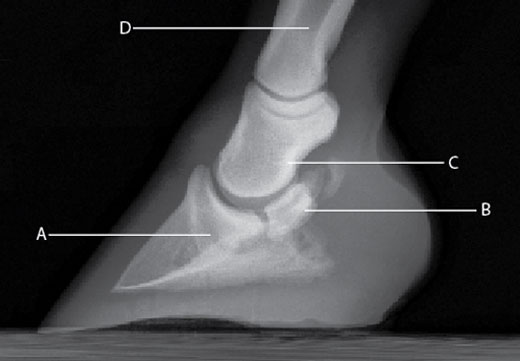

El síndrome navicular en los caballos es un arduo desafío en el tratamiento veterinario. Una forma de aliviar el dolor y reducir la inflamación asociada con esta condición consiste en inyectar un corticosteroide y ácido hialurónico —una combinación que tiene excelentes tasas de éxito a corto y a largo plazo— directamente en la bursa navicular. Puesto que la inyección en la bursa navicular es más difícil que la inyección en la articulación interfalángica distal (DIPJ, por sus siglas en inglés), el tratamiento sería más simple si los medicamentos pasaran siempre a través de la barrera biológica entre estos dos espacios sinoviales. Los dos espacios raramente se comunican de manera directa, pero las pequeñas sustancias de peso molecular se dispersarán en la bursa navicular desde la DIPJ. Sin embargo, las moléculas más grandes como el ácido hialurónico no pueden dispersarse. Un estudio en 11 caballos adultos clínicamente normales evaluó si la acetonida triamcinolona, un corticoesteroide comúnmente utilizado en el tratamiento del síndrome navicular, se dispersaría de la DIPJ a la bursa navicular, si la difusión sería directa o sistémica, y si la adición de ácido hialurónico afectaría esta difusión.

El estudio se realizó en dos fases. En la primera fase, se inyectó triamcinolona más solución de Ringer Lactato en la DIPJ de ambas extremidades anteriores de siete caballos. Se obtuvo el líquido sinovial de la bursa navicular a los 30 minutos y a una, tres, seis y nueve horas después de la inyección. Además, se evaluó este líquido para determinar en qué momento ocurrió la concentración más alta de triamcinolona. La concentración más alta de triamcinolona en la bursa navicular ocurrió seis horas después de la inyección en la DIPJ. En la segunda fase, se les inyecto a 11 caballos triamcinolona más solución de Ringer Lactato en una DIPJ de la extremidad anterior y una inyección de triamcinolona más ácido hialurónico en la otra extremidad anterior. Seis horas después de la inyección, se evaluó las muestras del líquido sinovial obtenidas de las bursas naviculares de las extremidades anteriores y posteriores de cada caballo. Las muestras de las extremidades posteriores sirvieron como un grupo de control sistémico ya que la absorción sistémica de la triamcinolona ocurre después de una inyección articular.

No se detectó triamcinolona en las muestras de la DIPJ previas a la inyección en los caballos de la segunda fase del estudio. Se encontró triamcinolona en todas las muestras de la bursa navicular de las extremidades posteriores después de la inyección y no se vio una diferencia significativa en las concentraciones de triamcinolona entre las extremidades anteriores que recibieron ácido hialurónico y aquellas que no. Se detectó una concentración significativamente mayor de triamcinolona en la bursa navicular de las extremidades anteriores que en la bursa navicular de las extremidades posteriores, lo cual representa un grado menor de absorción sistémica. La bursografía navicular realizada después de las inyecciones reveló que no existe ninguna comunicación directa entre la DIPJ y la bursa navicular. Aunque las concentraciones individuales de triamcinolona en el líquido sinovial variaron ampliamente, los resultados demuestran que la triamcinolona se difunde rápidamente entre la DIPJ y la bursa navicular de los caballos clínicamente normales y que la adición de una sustancia de alto peso molecular no afecta este movimiento. Estos resultados allanan el camino para nuevas investigaciones sobre los efectos, tanto positivos como negativos, del síndrome navicular en la permeabilidad de la membrana sinovial, la estructura de ácido hialurónico y el metabolismo de los fármacos en una articulación inflamada. Los profesionales de la veterinaria en equinos han sospechado desde hace tiempo que existe una relación, y ahora hay más datos que apoyan el tratamiento del síndrome navicular mediante inyecciones en la DIPJ.